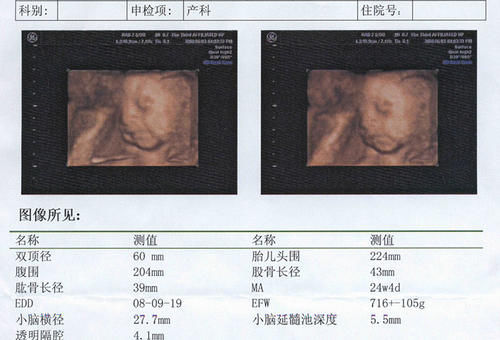

大多数人对于产检印象最深刻的无非就是四维彩超和B超,因为这两项产检项目都能够直接看到宝宝的模样。尤其是四维彩超,能够清晰地照到宝宝的五官。

腹部B超单

腹部B超主要是检查胎儿的胎心、胎芽、胎囊,孕妈如果想要知道宝宝的这三张指标是否正常,就需要在B超单上找出来,然后看一下数值是否在正常范围内。一般来说前面的是检查数据,后面会标注正常范围,孕妇自己对比一下就知道了。